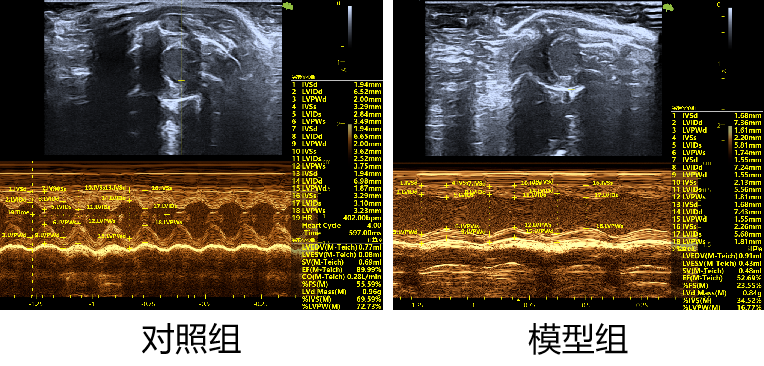

1.心脏超声检测

2.心肌组织HE染色